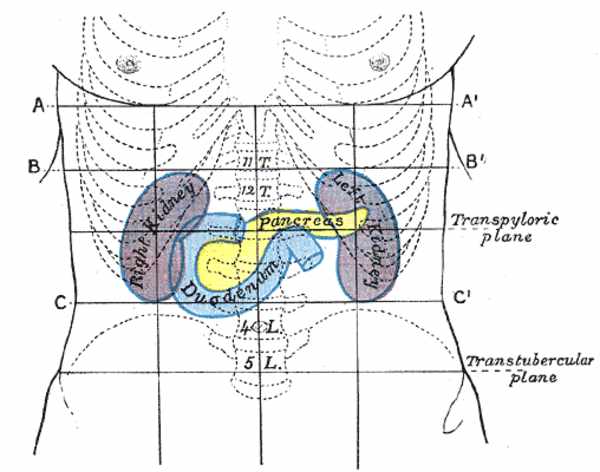

1889年2月21日

Reginald Fitz第一次完整的描述了胰腺炎,从最初的典型临床表现到死后的病理诊断。直到今天,胰腺炎依然是一个让人望而生畏的疾病。